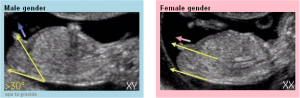

O tubérculo genital fetal é o projeto da genitália3, podemos dizer assim. Em meninos e meninas são muito parecidos até a 14ª semana e os médicos não conseguem diferenciar com certeza absoluta. Porém, alguns estudos mais aprofundados indicam que, dependendo da inclinação do ângulo do tubérculo genital fetal, pode-se saber sim se o sexo do bebê é masculino ou feminino. As imagens abaixo dão uma ideia de como saber o sexo dos bebê apenas pelo ângulo.

O tubérculo genital masculino tem uma angulação de 30º em relação à coluna do feto, enquanto que o tubérculo genital feminino é reto em relação à coluna. Simples e muito científico, porém para analisar o ângulo do tubérculo é preciso ter sorte no ultrassom e torcer para o bebê colaborar ao longo do exame. Veja meu ultrassom de 11 semanas. Dá para ver perfeitamente o tubérculo genital reto em relação à coluna.